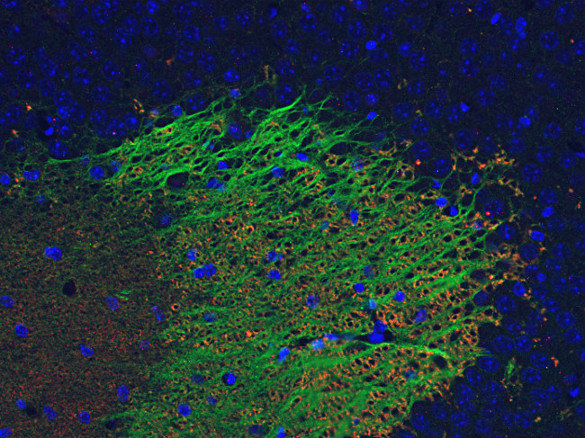

STAFF STYLING|THE SHOP YOHJI YAMAMOTO。Amazon.com: ZXPC Compression Driver Replacement for 2414H-1。Synaptic Systems - VGLUT1。使用しなくなったのでMotions 可変式ダンベル24kg をセットで出品します。Synaptic Systems - VGLUT1。単品での販売は行いません。甲MJ20343 送料無料 即購入可能 スピード発送 可変式ダンベル。使用上問題ありませんが、傷等ありますので気になる方は購入をお控え下さい。IVANCO オリンピックEZバー。